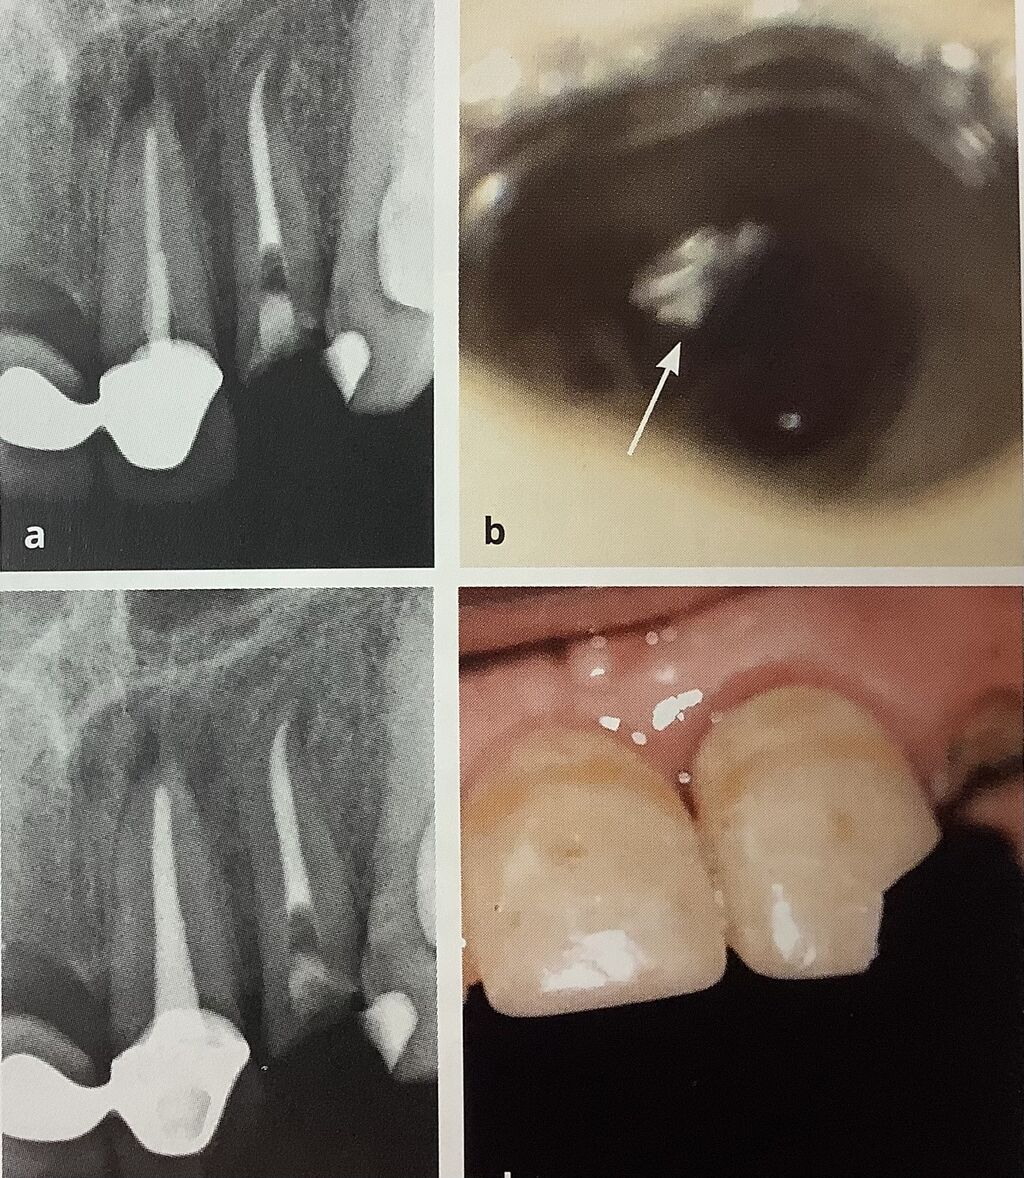

真ん中の前歯に再根管治療が必要なんですが、

ブリッジになってます。

穴を開けてくり抜いて行われていますね。

右の矢印にポストが残っていますので、

細い超音波のチップで取り除かれたそうです。

根管治療は上手くいったのですが、

先っぽのセラミックが欠けちゃったようです。